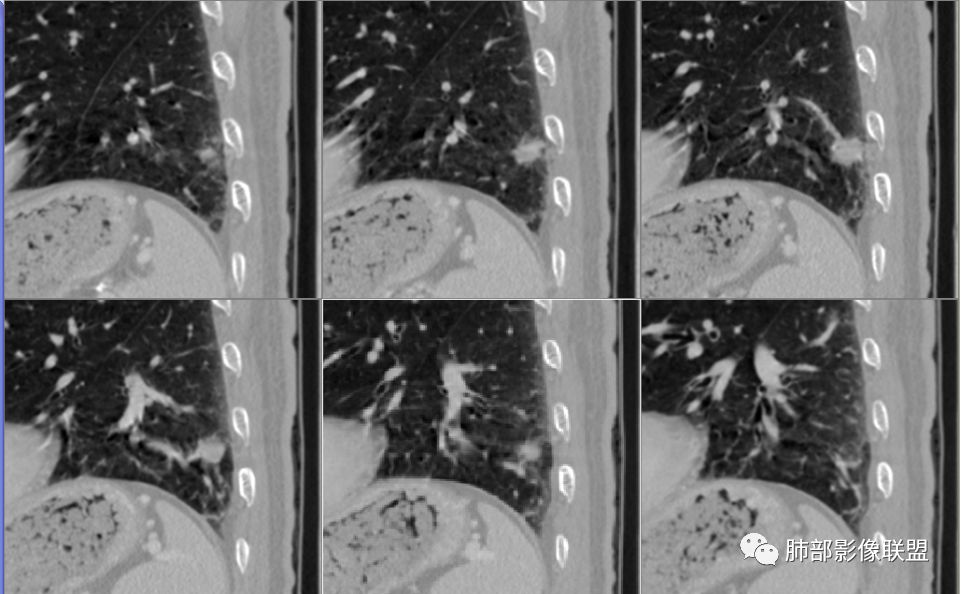

南大分析病例1

南边:

老年男性,因为头部症状来诊,也就是说肺部没症状

胸膜下结节,边界清楚、光滑,边缘稍凹陷,有胸膜牵拉

血管进入?

脐凹?

支气管在门口堵了

一般这类结节,边缘光滑

似有浅分叶

门口支气管堵塞——提示与支气管相关,不支持良性肿瘤

炎性?恶性?

符合炎性的地方:

实性,边缘凹陷,强化均匀

让我们不踏实的地方:

似乎有脐凹征

除了胸膜牵拉,还有短毛刺?血管纠集

支气管在门口堵塞

综合起来看,恶性不能排除。建议穿刺活检,一定要认清楚:我们影像有局限性。

应当说两例患者影像学表现都具有比较明显恶性征象,中老年男性患者,均都没有呼吸系统临床症状。

病例1为胸膜下实性小结节,血管脐凹样出入,可见支气管阻塞。病灶膨隆,部分边缘平直,周围晕征不明显,未见分叶,但可见毛刺及胸膜牵拉,增强后明显强化,老年男性,怀疑新生物尤其是腺癌是有理由的。